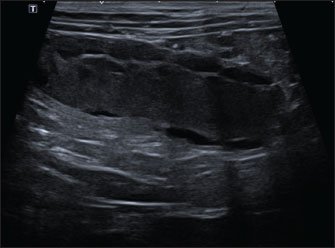

A Canon Aplio i600 ultrasound machine with convex (9-10.8 MHz) and linear (12-18 MHz) probes was used. The conscious patient was positioned in both the lateral and dorsal recumbencies. Moderate distension of both uterine horns (up to 17 mm in diameter) with immobile hyperechoic intraluminal content and irregular walls with multiple mural ovoid anechoic lesions were noted (Fig. 2). Cranial to the ovarian end of the right uterine horn and surrounding the right ovary, a 25-mm, well-defined, irregular lesion filled with mildly echogenic fluid was observed, which was compatible with a fluid-filled ovarian bursa. The adjacent peritoneum was moderately hyperechoic with a mild amount of free echogenic fluid (Fig. 3). A scant amount of free anechoic fluid was also present next to the uterine horns. A slightly tortuous tubular structure (up to 4 mm in diameter) with no color Doppler signal was identified running longitudinally adjacent to the ovary up to the uterine horn’s ovarian end, which was interpreted as the oviduct (Figs. 3 and 4). Moreover, both ovaries showed several rounded structures that were compatible with the corpora lutea. Vascularization near the lesion preserved the color Doppler signal.

Fig. 2. Abdominal ultrasonographic longitudinal examination in the left lateral recumbency using the B-mode with a microconvex probe. Cranial is to the left of the image. The right uterine horn is moderately distended with immobile hyperechoic intraluminal content and irregular walls with multiple mural ovoid anechoic lesions.